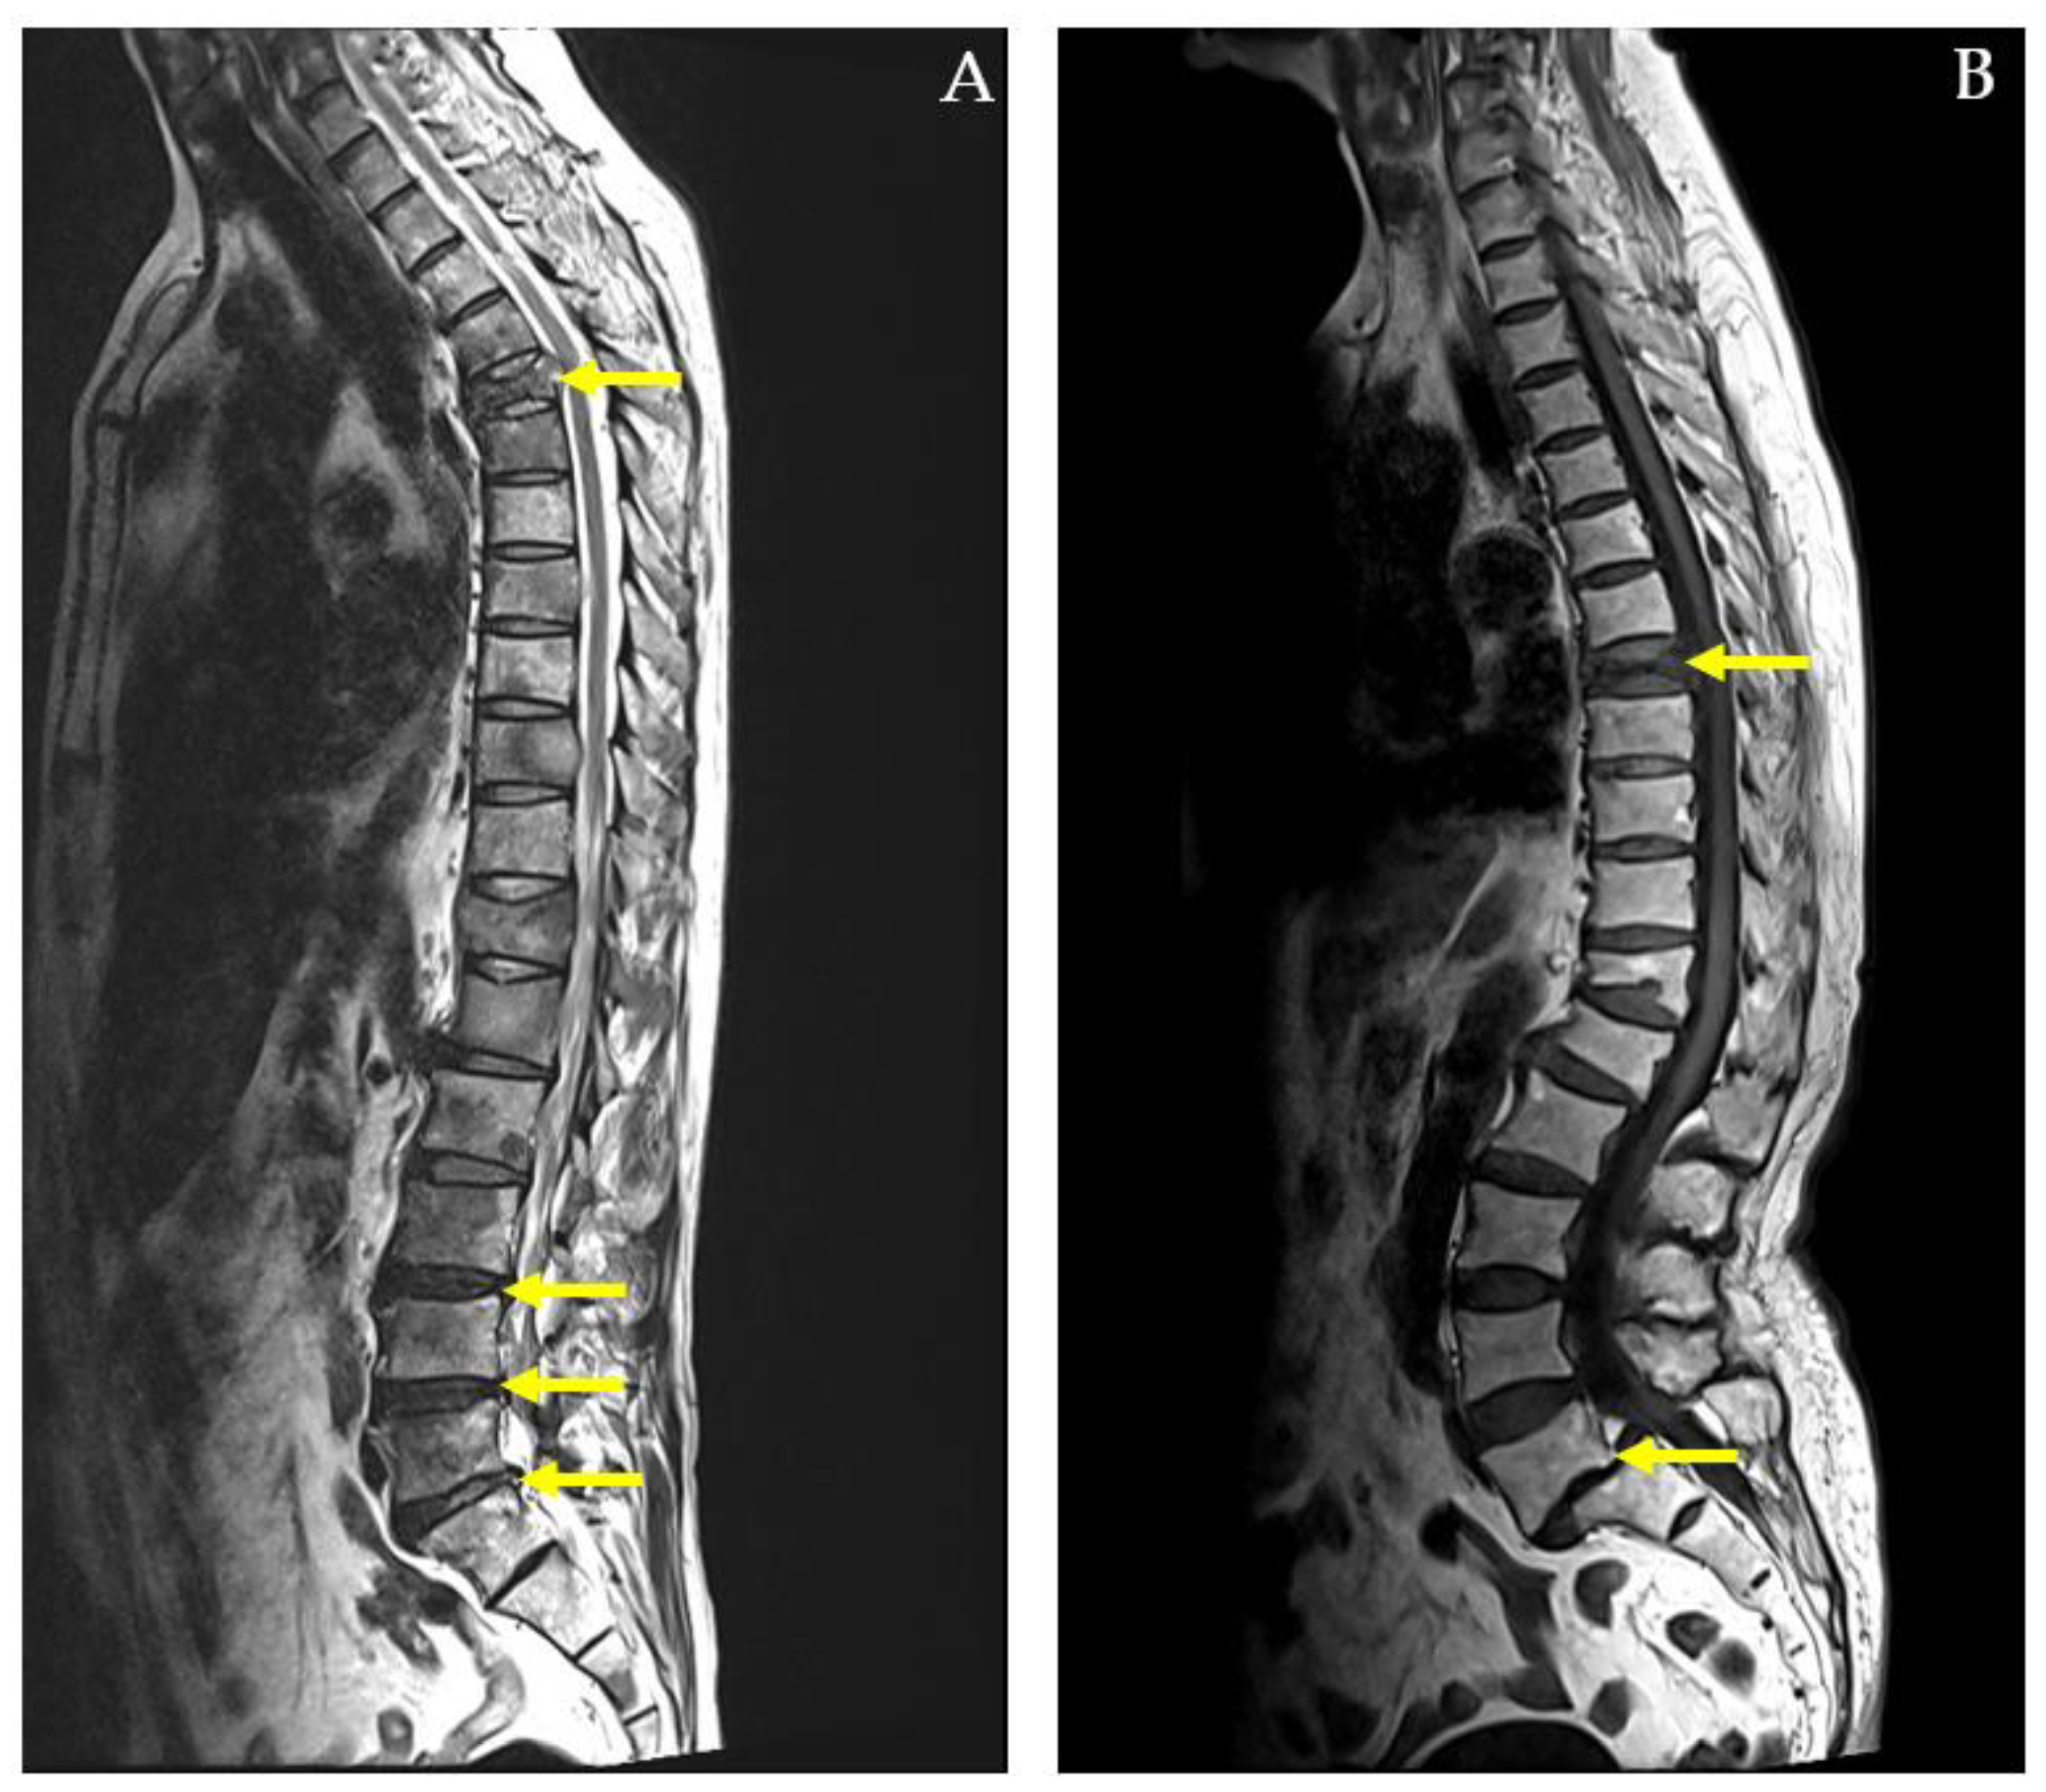

This research is important because it provides a pathway to more accurate, efficient, and cost-effective diagnostics for spinal conditions, enhances clinical decision-making, and contributes to the broader integration of machine learning into personalized healthcare. Furthermore, the study did not account for complex cases, such as those depicted in Figure 4, where patients presented with both pathological compression fractures and diffuse bony metastases, or with multiple spinal conditions like spondylolytic spondylolisthesis.

While the SVM model provides useful classification results, its lack of interpretability in comparison to simpler models like logistic regression may limit its clinical utility. Clinicians may require more transparent models that provide clear explanations for their predictions. Thus, future work could focus on developing interpretable machine learning models that offer high accuracy without sacrificing transparency. Furthermore, the study did not account for complex cases, where patients presented with both pathological compression fractures and diffuse bony metastases, or with multiple spinal conditions like spondylolytic spondylolisthesis. These more complicated cases were not fully addressed in the model, which could limit its application in more severe or multifactorial clinical scenarios. Future studies should incorporate these complex cases to improve the model’s comprehensiveness and clinical relevance.

Figure 4. MRI whole-spine imaging demonstrating pathological compression fractures, herniated intervertebral discs (HIVDs), and spondylolisthesis indicated by yellow arrows. In (A) a 59-year-old male diagnosed with lung cancer and diffuse bony metastases affecting the cervical, thoracic, lumbar spine, sacrum, bilateral iliac bones, and right femoral head. The MRI reveals a pathological compression fracture of the T5 vertebral body with associated spinal cord compression. Additionally, herniated intervertebral discs (HIVDs) are present at the L3-L4, L4-L5, and L5-S1 levels. In (B) an 87-year-old female with a compression fracture at the T8 vertebral body. The MRI also shows L5-S1 spondylolytic spondylolisthesis with narrowing of bilateral neural foramina.